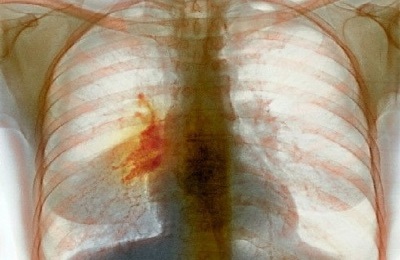

Диагностируется легочная онкология несколькими способами:

- МРТ и КТ.

- Рентгенография.

- Биопсия и гистология биоматериалов.

- Бронхоскопия.

- Анализ крови на онкомаркеры.

Для получения наиболее достоверных данных выше перечисленные обследования могут назначаться комплексно в определенной совокупности.

При обследованиях раковое разрастание имеет внушительные размеры – более 7 см. отмечаются метастазы не только на соседнем легком, но и на близ расположенных органах – трахее, пищеводе, сердце, диафрагме и т.п.